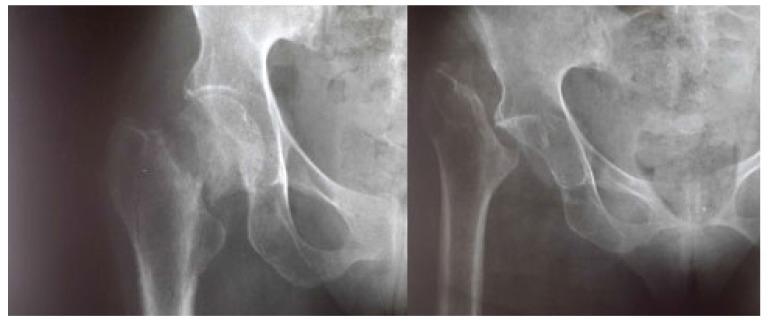

Head and neck resection of the femur was described by Girdlestone in 1928 in the treatment of coxalgia. Very invasive at the beginning, this intervention is much less so today, but the term of "Girdlestone's operation" or "Girdlestone's procedure" has remained in use. The reported results are controversial. In resource-limited countries, Girdlestone's procedure is often indicated for lack of a better one. In this context, we report the results of a series of 24 patients operated in a regional hospital (Ouahigouya, Burkina Faso) with the aim of showing that this technique remains valid and can be benefit.

This was a retrospective descriptive study of 24 patients who had benefited from the procedure for cervical fracture sequelae, failure of arthroplasty or osteosynthesis, or osteonecrosis. All were operated by posterolateral approach, under spinal anesthesia and followed for 5 years with evaluation of the anatomical and functional results using the rating of Postel and Merle d'Aubigné (PMA).

All patients had Trendelenburg lameness with a mean shortening of 3.5 cm. They were all autonomous with walking aids and the PMA score ranged from 16 to 14. Discussion: although the results obtained are not excellent, they are relatively good and have allowed all our patients to recover an acceptable autonomy, compatible with certain independence in everyday life.

1928年,格德尔斯通(Girdlestone)描述了股骨的头颈切除术用于治疗髋关节疼痛。该手术最初具有很强的侵入性,如今则不然,但“格德尔斯通手术”或“格德尔斯通术式”这一术语仍在使用。报道的结果存在争议。在资源有限的国家,由于缺乏更好的选择,格德尔斯通术式常被采用。在此背景下,我们报告了在一家地区医院(布基纳法索瓦希古亚)对24例患者进行手术的结果,旨在表明该技术仍然有效且有益。

这是一项对24例因颈椎骨折后遗症、关节置换术或骨固定术失败或骨坏死而接受该手术的患者的回顾性描述性研究。所有患者均采用后外侧入路,在脊髓麻醉下进行手术,并随访5年,使用波斯特尔(Postel)和梅尔·德奥比涅(Merle d'Aubigné)评分(PMA)评估解剖和功能结果。

所有患者均有臀中肌麻痹跛行,平均肢体短缩3.5厘米。他们在使用助行器的情况下均能自主活动,PMA评分在16至14分之间。讨论:尽管所获得的结果并不理想,但相对较好,使我们所有的患者都恢复了可接受的自主能力,与日常生活中的一定独立性相符。